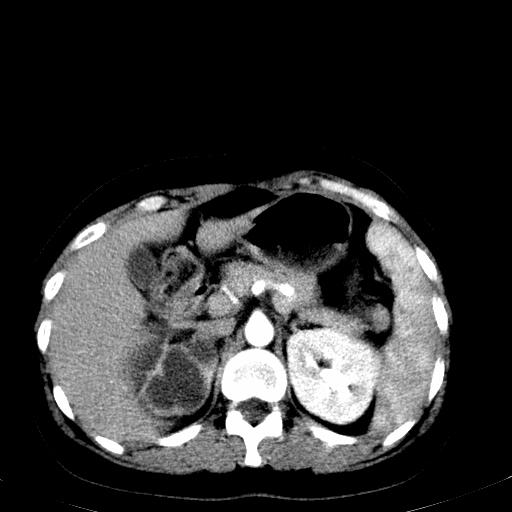

患者体检发现右肾体积增大,怀疑右肾积水

右肾重度积水,以肾盏积水明显,有分隔,上段输尿管轻度扩张,管壁增厚,考虑肾结核可能,请结合尿检查,胸部拍片排除肺结核。

右肾重度积水,建议ct向下扫描或逆行造影,左肾及左输尿管结石 .

1)不排除右肾结核可能。2)左肾及左输尿管上段结石?

要排除右肾结核可能

左肾不是结石,是造影后改变.右肾积水,功能仅存.